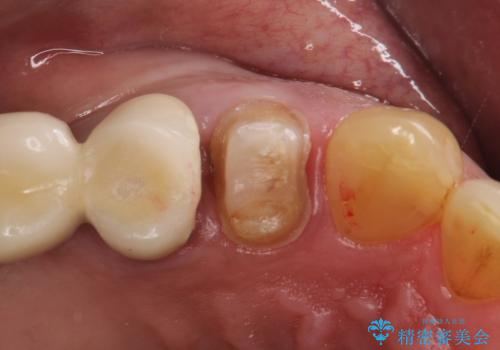

- 以前治療したセラミックインレーが破折したことを主訴に来院されました。

咬合力が強く、残存歯質が少ないためオールセラミッククラウンによる治療を行いました。